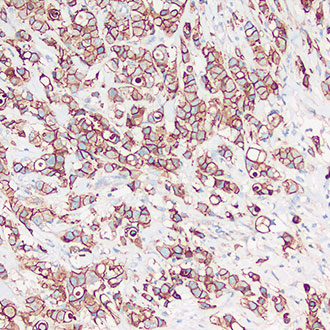

E-Cadherin

E-Cadherin -